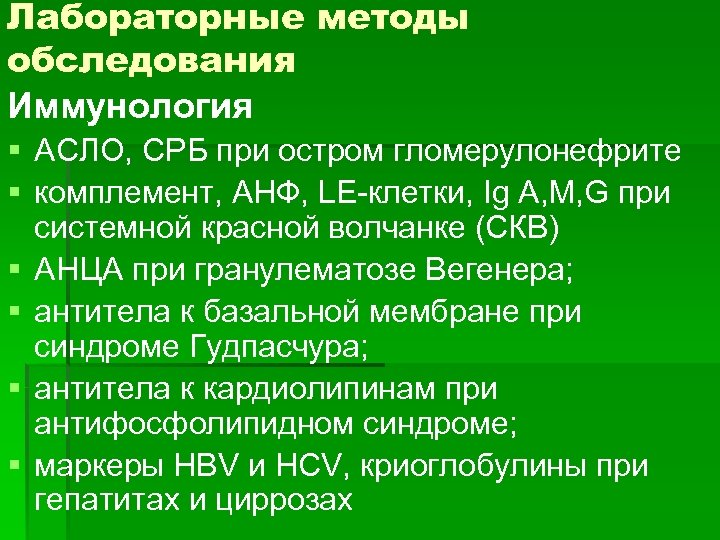

Лабораторные методы обследования Иммунология § АСЛО, СРБ при остром гломерулонефрите § комплемент, АНФ, LE-клетки, Ig A, M, G при системной красной волчанке (СКВ) § АНЦА при гранулематозе Вегенера; § антитела к базальной мембране при синдроме Гудпасчура; § антитела к кардиолипинам при антифосфолипидном синдроме; § маркеры HBV и HCV, криоглобулины при гепатитах и циррозах